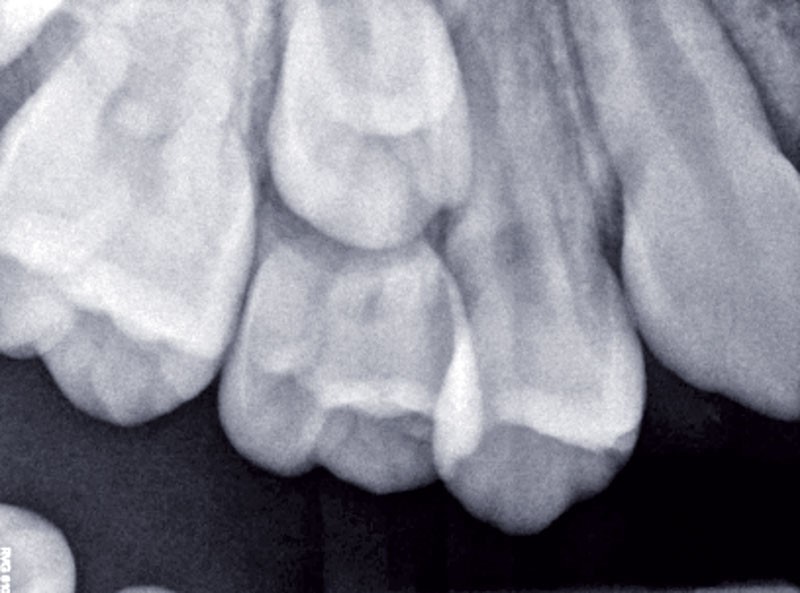

Un cliché rétro-alvéolaire et un orthopantomogramme confirment un processus de rhyzalyse physiologique de 55, comparable à celui de sa contro-latérale.